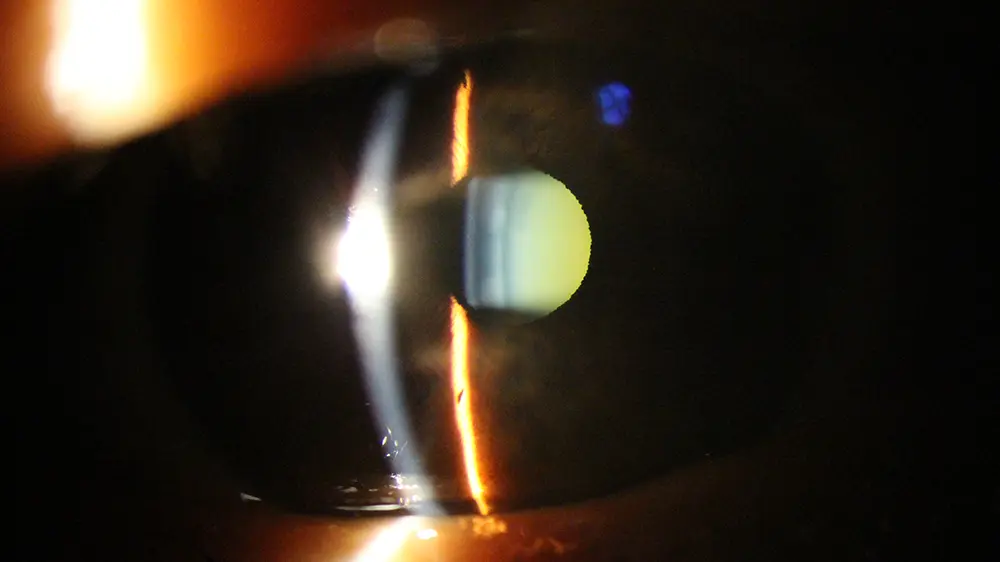

Catarata é o nome que se dá ao cristalino (lente natural de nossos olhos) que perdeu a transparência (geralmente pela idade, ocorrência de certas doenças como o diabetes ou trauma ocular, uso de certos medicamentos entre outras causas). Na figura, pode-se notar o aspecto esbranquiçado que a catarata pode dar à pupila.